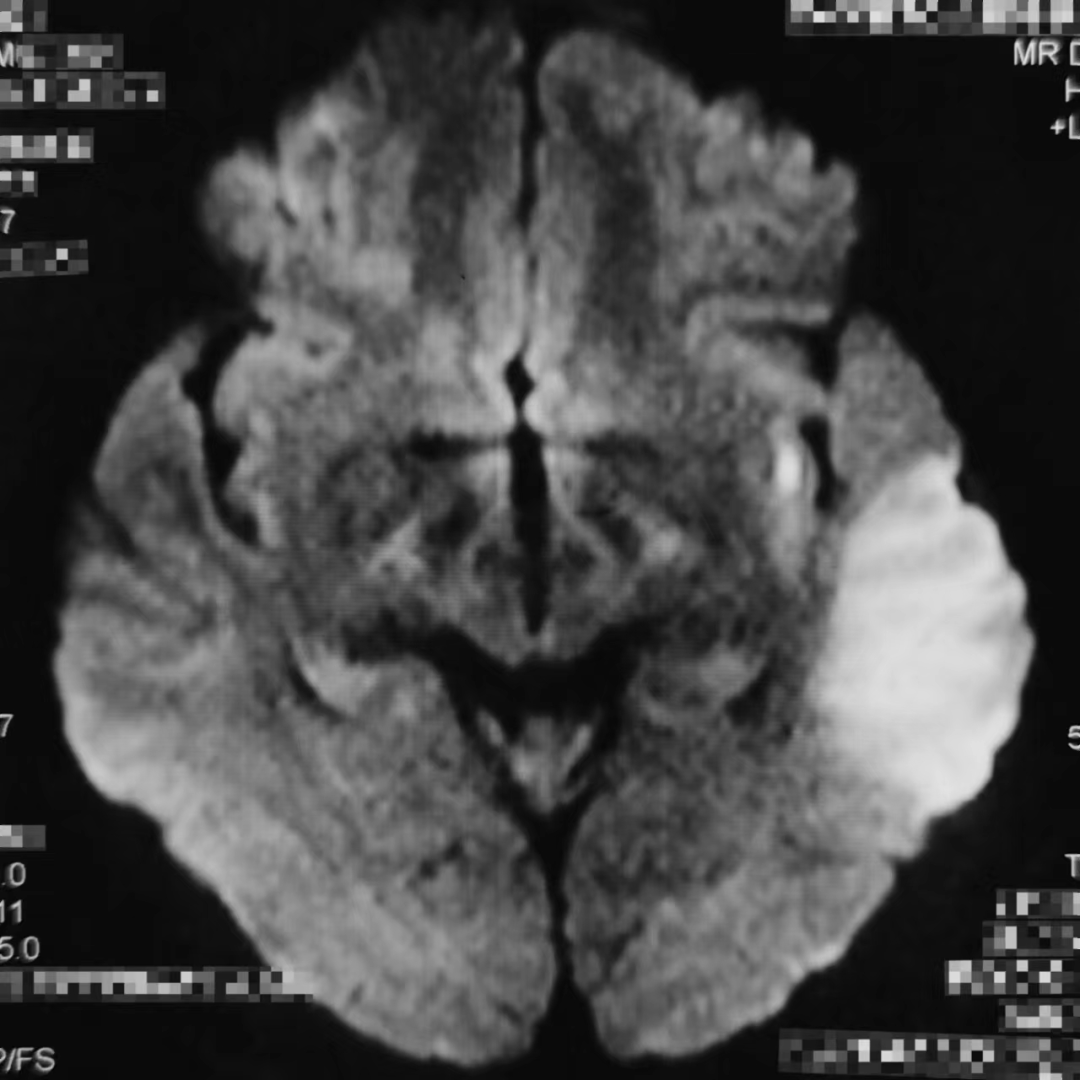

什么叫桡鞘Epath®长鞘经桡入路丨冯军教授团队:Epath®长鞘经桡入路行颈动脉狭窄CAS术一例_https://www.jmylbn.com_新闻资讯_第5张

脑部MR示:左侧颞叶梗塞灶